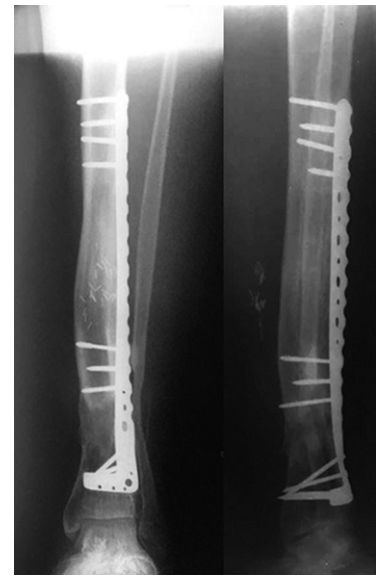

等确定感染控制了,软组织条件好了,行II期手术,本文作者介绍了一种组合式固定方式+骨搬运。

➤ 1、骨科外固定支架单边(用于骨搬运+支撑);

➤ 2、锁定长钢板(维持长度+支撑);

➤ 3、I期术后12个月,搬运到位后,直接上螺钉固定,去除外固定架。